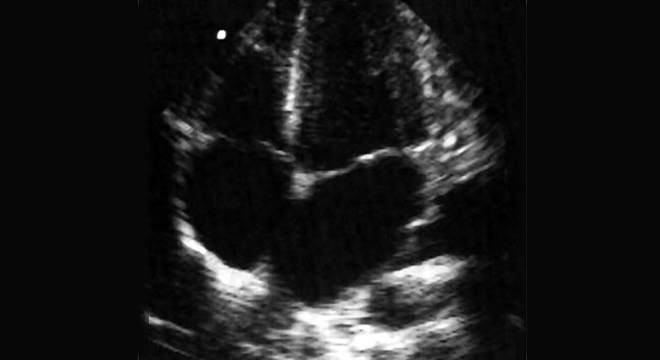

- Herz-Ultraschall (Echokardiographie )